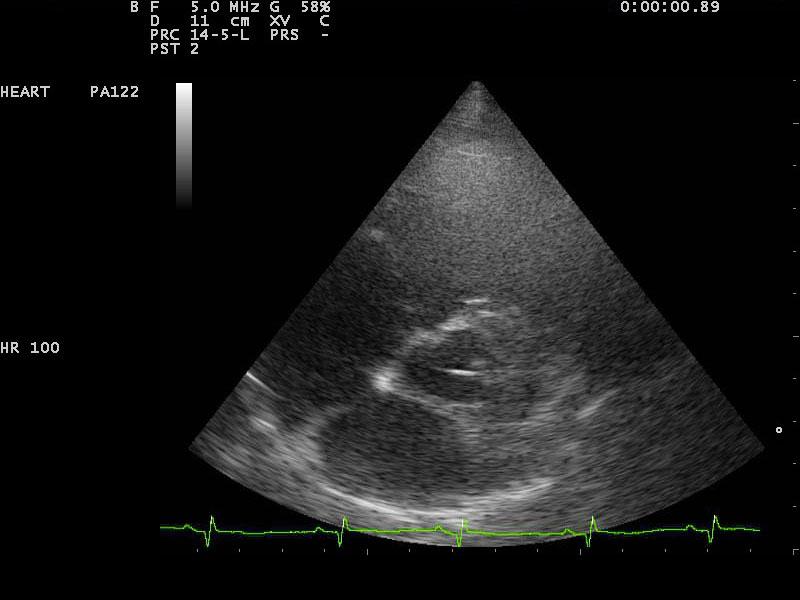

A 10-year-old SF Labrador was presented for evaluation of ascites, which was quantified as a modified transudate. Additional history on this dog was that 11 months prior an ovariohysterectomy and resection of mammary gland tumors had been done. The tumors were benign on histopathology. On abdominal ultrasound, the ascites, hepatic congestion, and a dilated CVC were present.